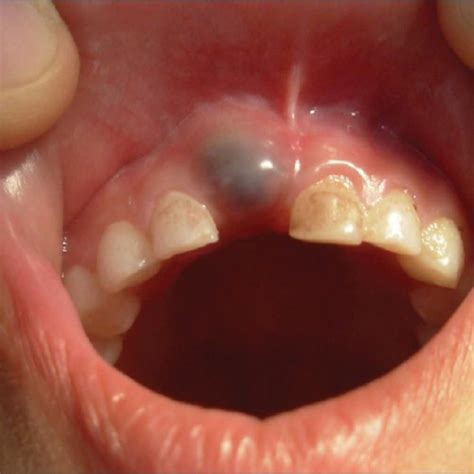

An eruption cyst is a benign swelling in the mouth that occurs when a tooth is about to emerge. It presents as a small bluish bubble on the gums and is filled with fluid.

Eruption cysts occur when the tooth underneath the gum starts to push through the soft tissue. The fluid-filled cyst is a result of the pressure build-up.